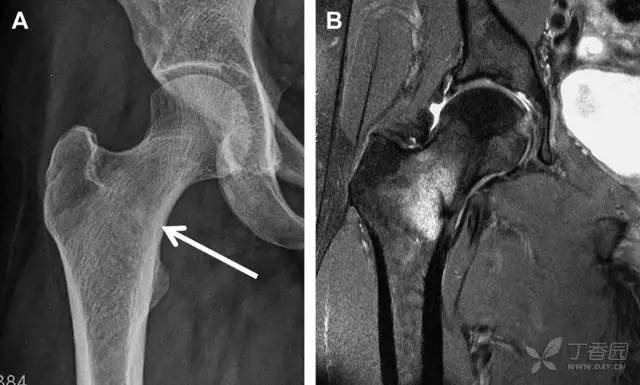

股骨颈应力性骨折在参加耐力运动的运动员中常见,且常发生在股骨颈压力侧。股骨颈基底部发现一垂直于骨皮质的线性硬化带可诊断这种类型的劳累性骨折(图 8)。

图 8 长跑运动员股骨颈应力性骨折。X 片(A)和冠状位 CT 多维重建(B)图像示穿过股骨颈内侧皮质中的透亮区(箭头),周围硬化。骨折垂直于皮质

股骨颈张力侧的应力性骨折有可能发展为完全骨折(图 9)。

图 9 进食障碍患者股骨颈应力性骨折的张力侧。A 正位片示股骨颈完全骨折。B 2 周前的 X 片示局部骨量减少,正是后来发生骨折的位置(箭头)